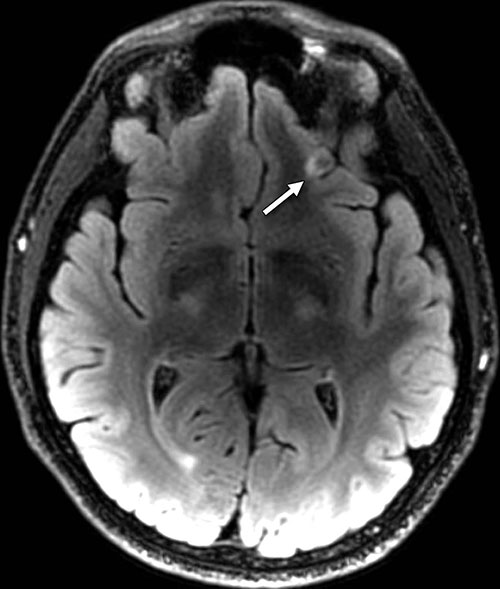

The participants were diagnosed with predominantly chronic (mean, 1,381 days; median, 888 days after injury) and mild (92 percent [768 of 834]) TBI. Of these participants, 84.2 percent (688 of 817) reported one or more blast-related incident and 63.0 percent (515 of 817) reported loss of consciousness at the time of injury. The presence of white matter T2-weighted hyper-intense areas was the most common pathologic finding, observed in 51.8 percent (432 of 834; OR, 1.75) of TBI participants. Cerebral microhemorrhages were observed in a small percentage of participants (7.2 percent [60 of 834]; OR, 6.64) and showed increased incidence with TBI severity (P < .001, moderate and severe vs. mild). T2-weighted hyper-intense areas and microhemorrhages did not collocate by visual inspection. Pituitary abnormalities were identified in a large proportion (29.0 percent [242 of 834]; OR, 16.8) of TBI participants.